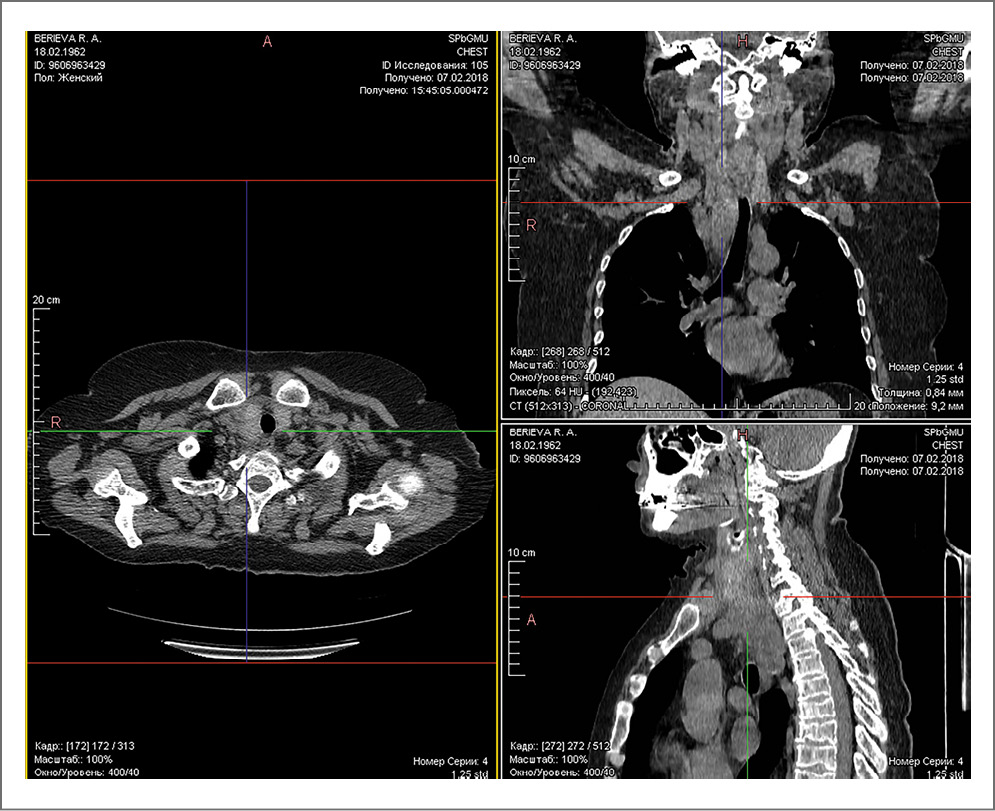

В плановом порядке выполнена паратиреоидэктомия. Интраоперационно у нижнего полюса правой доли ЩЖ определялось образование размерами 3,0×3,5×5,0 см, сходное с описанием на УЗИ органов шеи, которое удалено. Однако уровень операционного паратгормона не снизился через 15 мин и составлял 3000 пг/мл. При ревизии и интраоперационном УЗИ шеи образований в проекции нижнего полюса правой доли ЩЖ не выявлено. Принято решение завершить операцию и провести дообследование в послеоперационном периоде. При контрольном УЗИ шеи данных за объемные образования не получено, но, учитывая отсутствие снижения уровня ПТГ в послеоперационном периоде и вероятность эктопии ПЩЖ, принято решение выполнить мультиспиральную компьютерную томографию (МСКТ) шеи (рис. 2), при которой у нижнего полюса правой доли ЩЖ определялось образование размерами 3,0×4,0×7,0 см, спускающееся в верхнее средостение до ThI, полуциркулярно обхватывающее трахею сзади. Учитывая эти данные, принято решение о выполнении повторного оперативного вмешательства.

Рис. 2. МСКТ шеи.